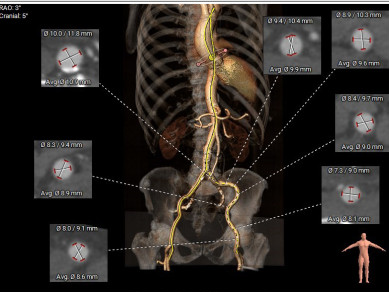

患者术前CT分析:主动脉瓣为三叶式,瓣叶增厚;主动脉弓角度偏小。

瓣环

窦部大小

左室流出道

升主动脉

瓣叶开放3D图

外周血管